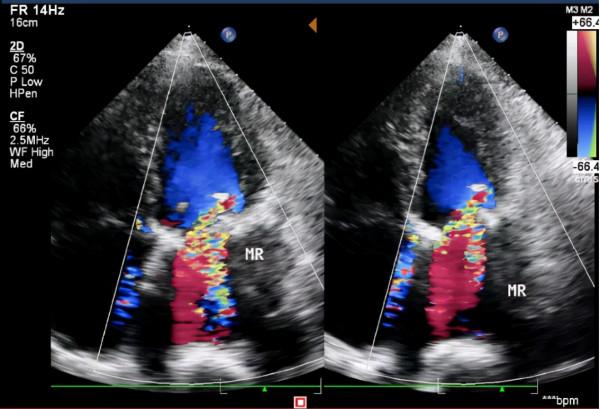

農姥姥入院後,多學科專家評估,發現農姥姥不只生物二尖瓣衰敗、狹窄返流嚴重,而且它的主動脈瓣也出現了較重的風溼性鈣化,心臟收縮功能明顯減低(EF:34-46%)。加上自身基礎疾病很多,屬於外科手術的高危病例,如果再次開胸手術,風險很大,很可能出現各種不良併發症而危及生命。

吳棘主任開展食道超聲和DSA實時評估,兩個介入瓣膜位置良好,啟閉正常,跨瓣壓差明顯減輕,無瓣周漏,這標誌著手術成功完成。術後,農姥姥一般情況穩定。